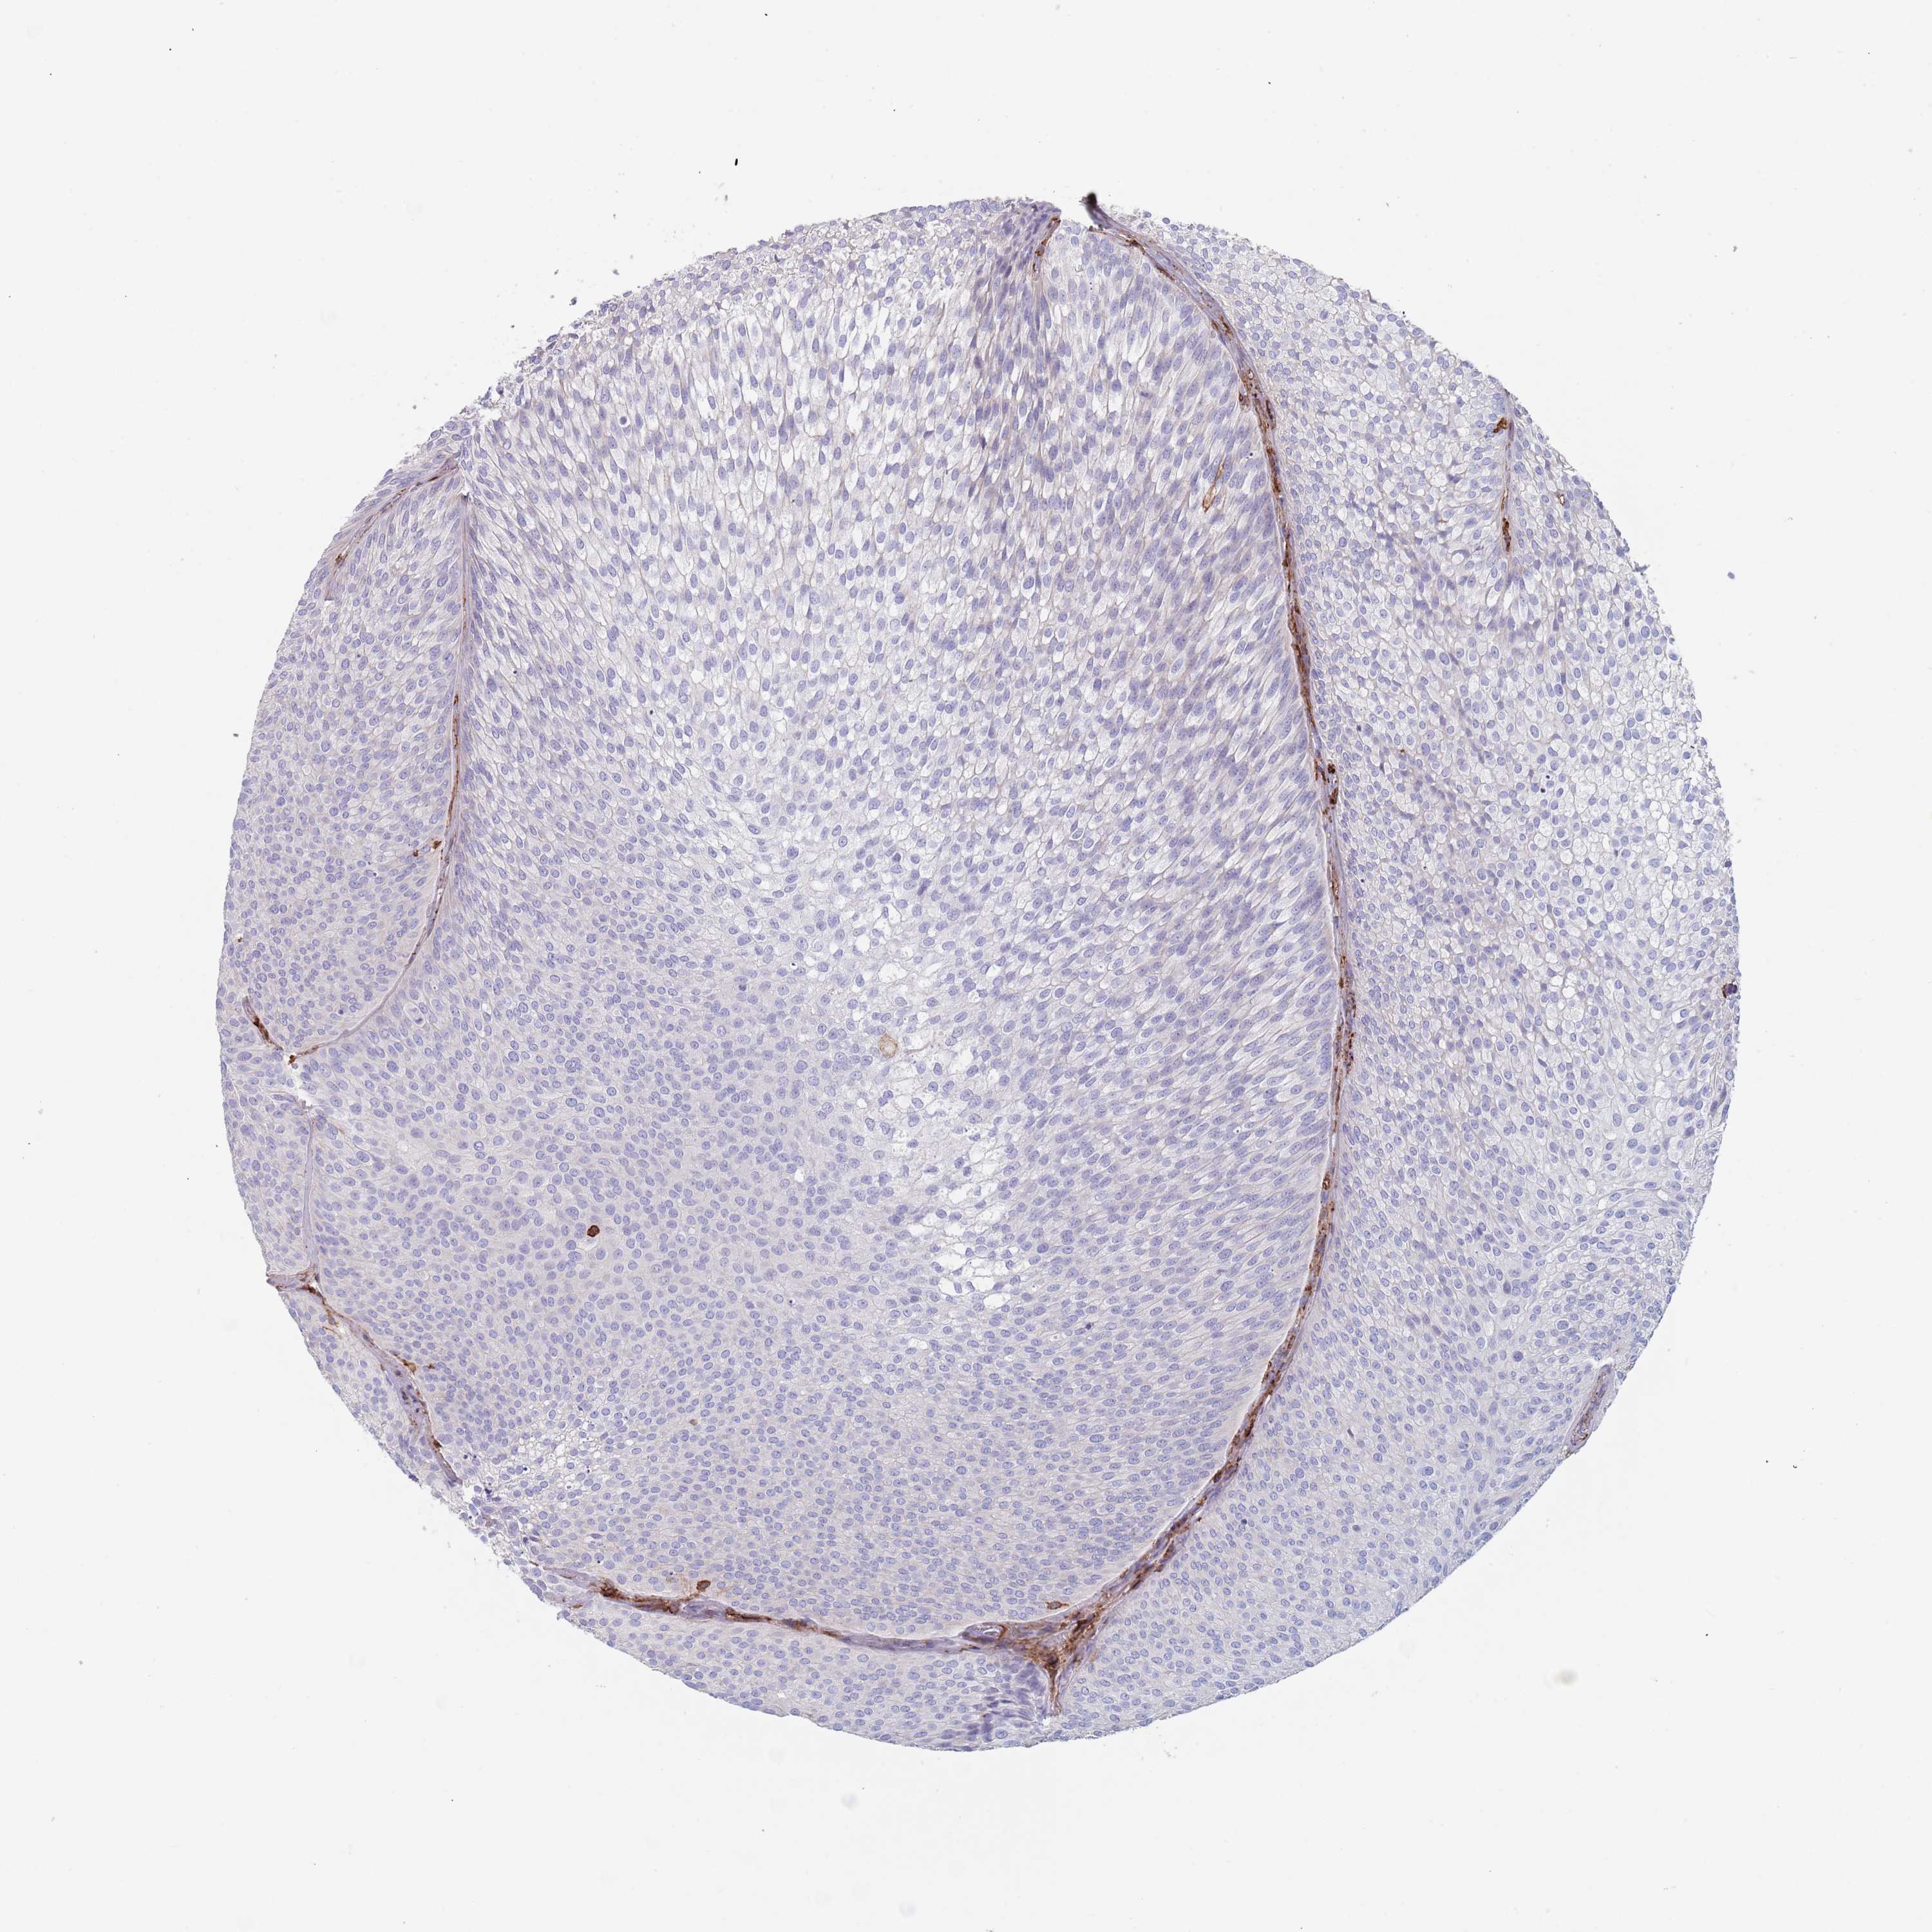

UROTHELIAL CANCER - Protein expressioni

A mouse-over function shows sample information and annotation data. Click on an image to view it in a full screen mode. Samples can be filtered based on level of antibody staining by selecting one or several of the following categories: high, medium, low and not detected. The assay and annotation is described here.

Antibody stainingi

Antibody staining in the annotated cell types in the current human tissue is reported as not detected, low, medium, or high, based on conventional immunohistochemistry profiling in selected tissues. This score is based on the combination of the staining intensity and fraction of stained cells.

Each image is clickable and will lead to virtual microscopy that enables deeper exploration of all samples and also displays staining intensity scores, fraction scores and subcellular localization as well as patient and tissue information for each sample.

Antibody HPA049939

Staining

High

Medium

Low

Not detected

Intensity

Strong

Moderate

Weak

Negative

Quantity

>75%

75%-25%

<25%

None

Location

Nuclear

Cytoplasmic/membranous

Cytoplasmic/membranous,nuclear

Urothelial carcinoma, Low grade

Urothelial carcinoma, High grade

Urothelial carcinoma, NOS